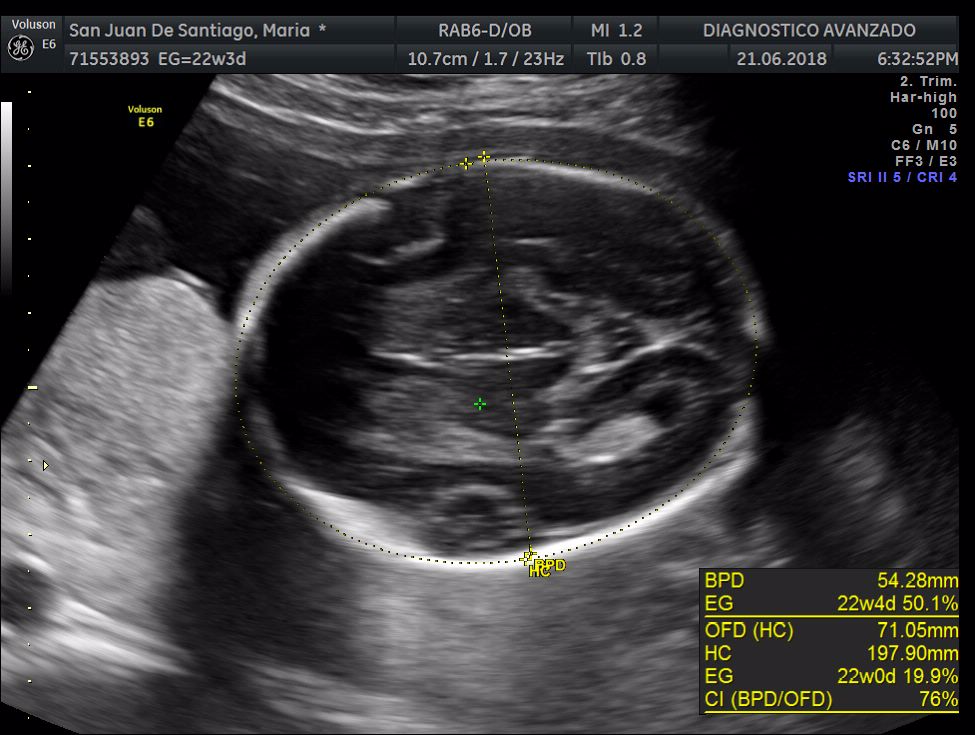

¡Hola a todos! Hoy hemos ido a hacer la tradicional ecografía 3D de la niña, os dejamos todo el material (aunque es un poco demasiado).